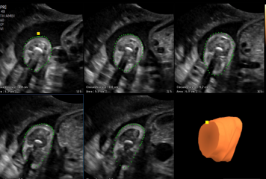

5D NTTM

5D NTTM permite la visualización automática del plano sagital medio del feto para medir la translucencia nucal (NT), lo que facilita la evaluación del riesgo cromosómico y apoya la toma de decisiones clínicas tempranas en obstetricia.

5D Follicle™ y 2D Follicle™

Estas herramientas permiten evaluar el tamaño y estado de los folículos ováricos, facilitando la planificación de ciclos de estimulación controlada y tratamientos de fertilidad con precisión y seguridad.